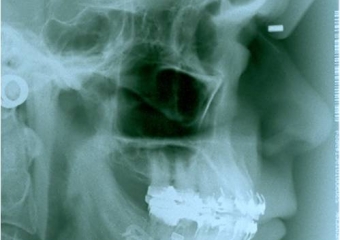

Telerradiografia inicial